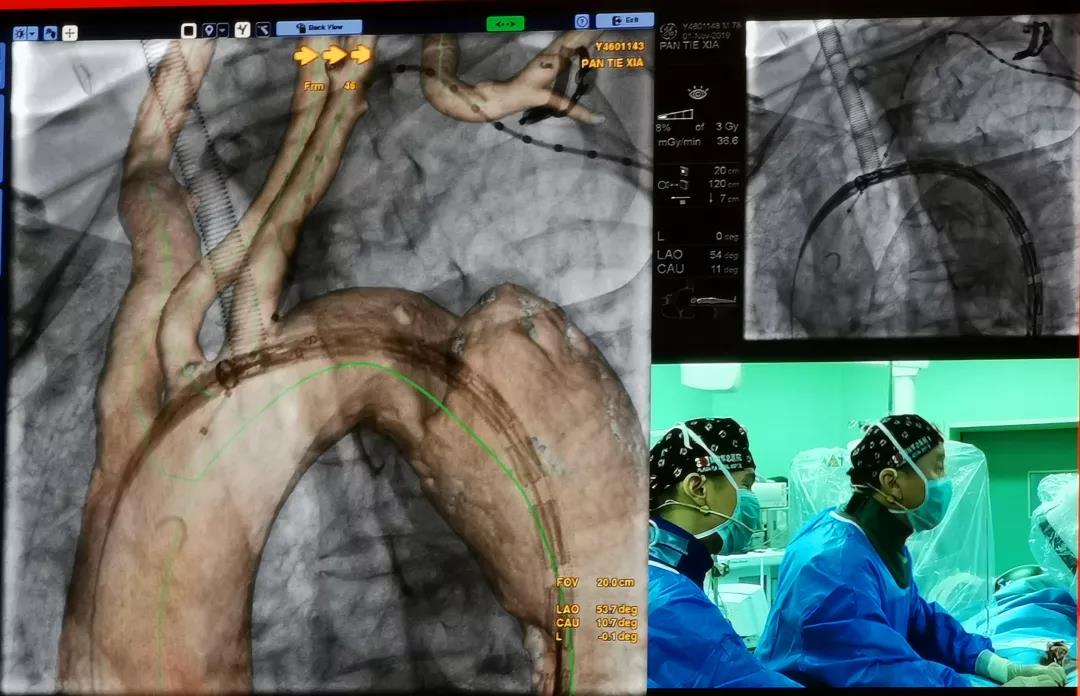

中国人民解放军总医院郭伟教授共演示了3台手术,分别是采用Ankura™支架治疗Stanford B型慢性胸主动脉夹层,采用Lifeflow™IBD髂动脉分叉支架系统和Fustar™可调弯鞘在治疗腹主动脉瘤时重建右侧髂内动脉的病例。另外,郭伟教授还演示了一台使用Ankura™支架和新型G-Branch™胸腹主动脉覆膜支架系统重建内脏动脉全腔内修复胸腹主动脉瘤的病例。郭教授从患者病变情况和治疗难点、手术方案、G-Branch™支架产品设计特点及术中操作要点等方面详细介绍了手术过程。手术取得了极大的成功,术后造影显示,瘤体隔绝,内脏四分支血管血流通畅,且主体支架与分支支架连接处无内漏。与会专家对此精彩的病例表示尤为赞叹,积极与郭伟教授探讨G-Branch™支架的创新之处和未来使用方向。郭教授表示,多分支动脉的腔内重建是胸腹主动脉瘤微创治疗的一个技术高地,也是国际性难题。G-Branch™支架的应用,为胸腹主动脉瘤的患者提供了更为优秀的解决方案,期待未来更多的临床应用和循证医学证据将证实其优越性。

中国人民解放军总医院手术录播《G-Branch™多分支支架治疗胸腹主动脉瘤》